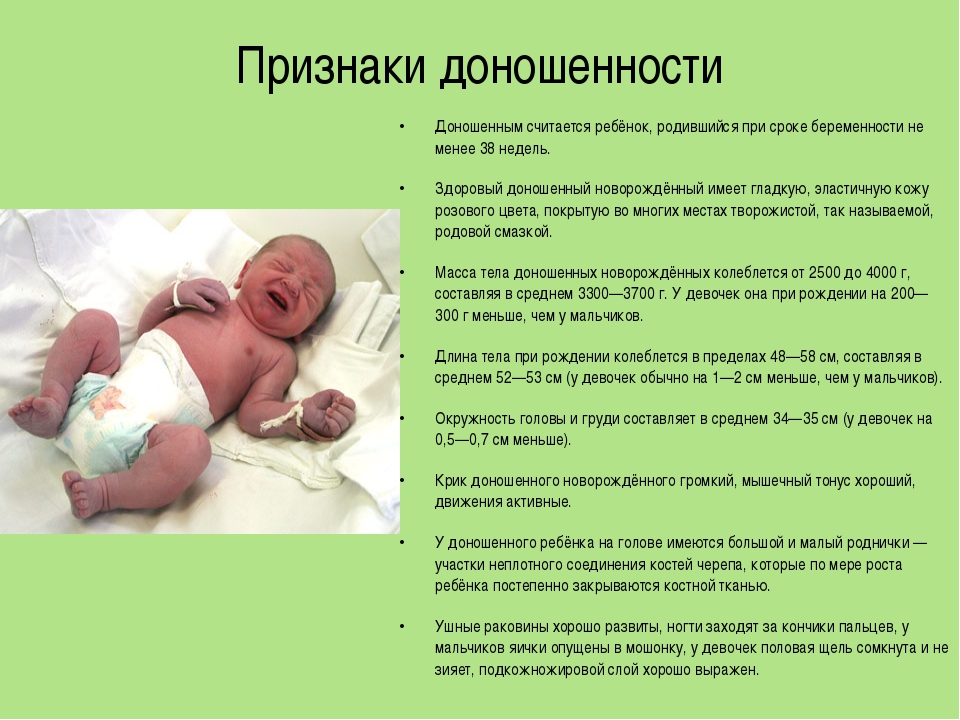

38 nedelya beremennosti 64 foto chto proishodit s malyshom i mamoj predvestniki rodov u povtornorodyashih i pervorodyashih seks i priznaki priblizhayushihsya rodov vtoraya beremennost toshnota i ponos izzhoga na 38 akusherskoj nedele (Тип файла jpg)

38 Nedelya Beremennosti 64 Foto Chto Proishodit S Malyshom I Mamoj Predvestniki Rodov U Povtornorodyashih I Pervorodyashih Seks I Priznaki Priblizhayushihsya Rodov Vtoraya Beremennost Toshnota I Ponos Izzhoga Na 38 Akusherskoj Nedele